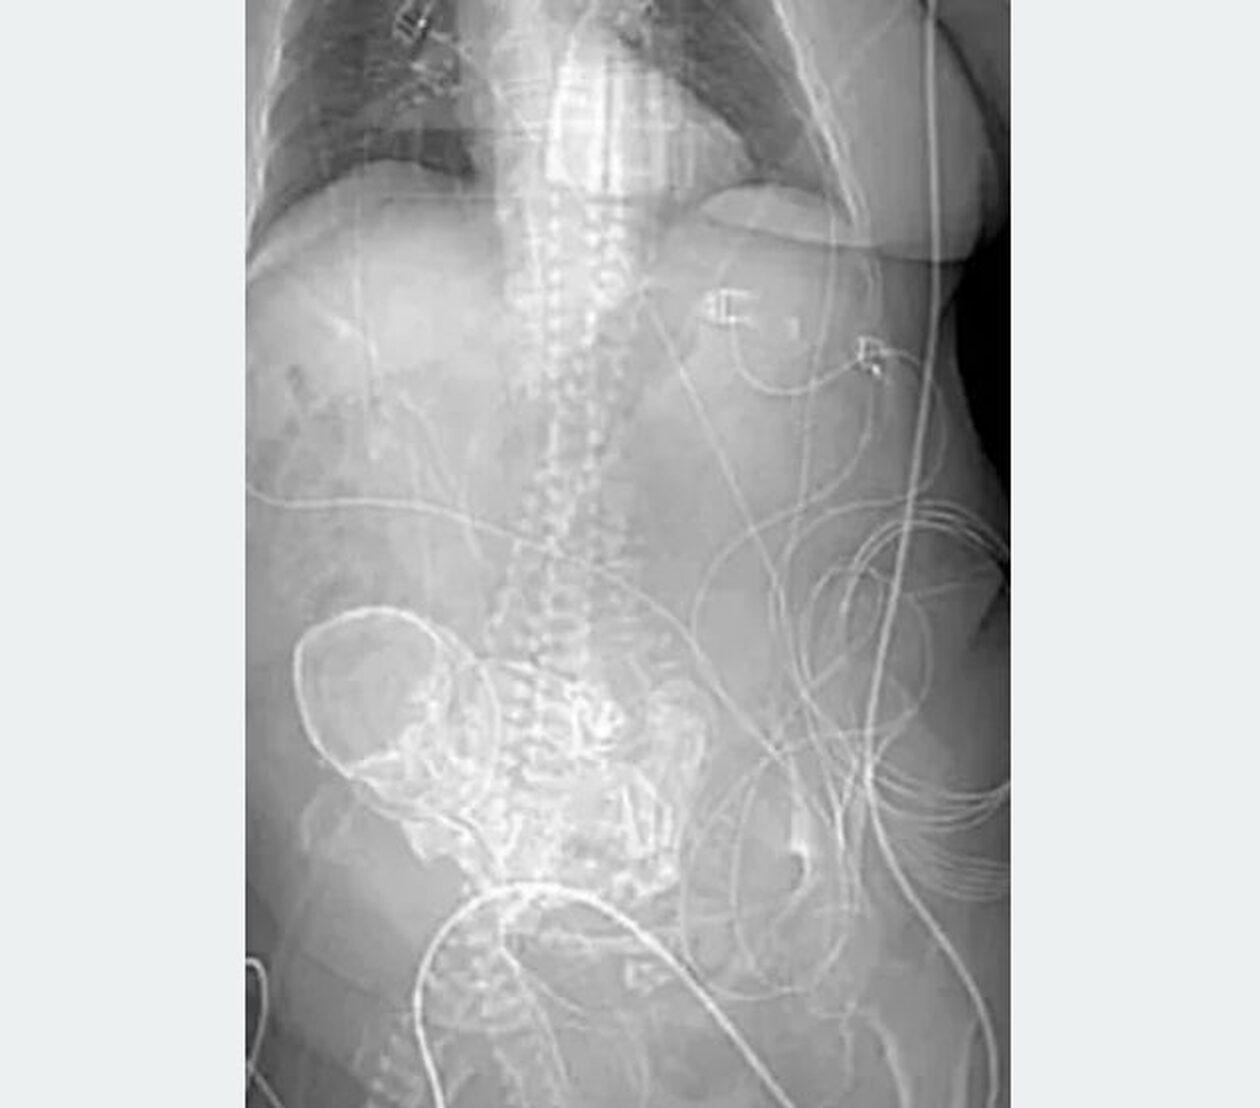

Ήταν το αποτέλεσμα ενός σπάνιου τύπου εξωμήτριας εγκυμοσύνης, γνωστής ως λιθοπεδίου, όπου το έμβρυο πεθαίνει αλλά δεν μπορεί να απορροφηθεί εκ νέου από το σώμα της μητέρας.

Αντίθετα, το νεκρό έμβρυο συγκρατείται στην κοιλιακή κοιλότητα, σχηματίζοντας ένα περίβλημα ασβεστίου γύρω του. Η τομογραφία λήφθηκε αφού μεταφέρθηκε επειγόντως στο Περιφερειακό Νοσοκομείο Ponta Pora στην κεντροδυτική πολιτεία Mato Grosso do Sul της Βραζιλίας με γενικευμένη λοίμωξη.